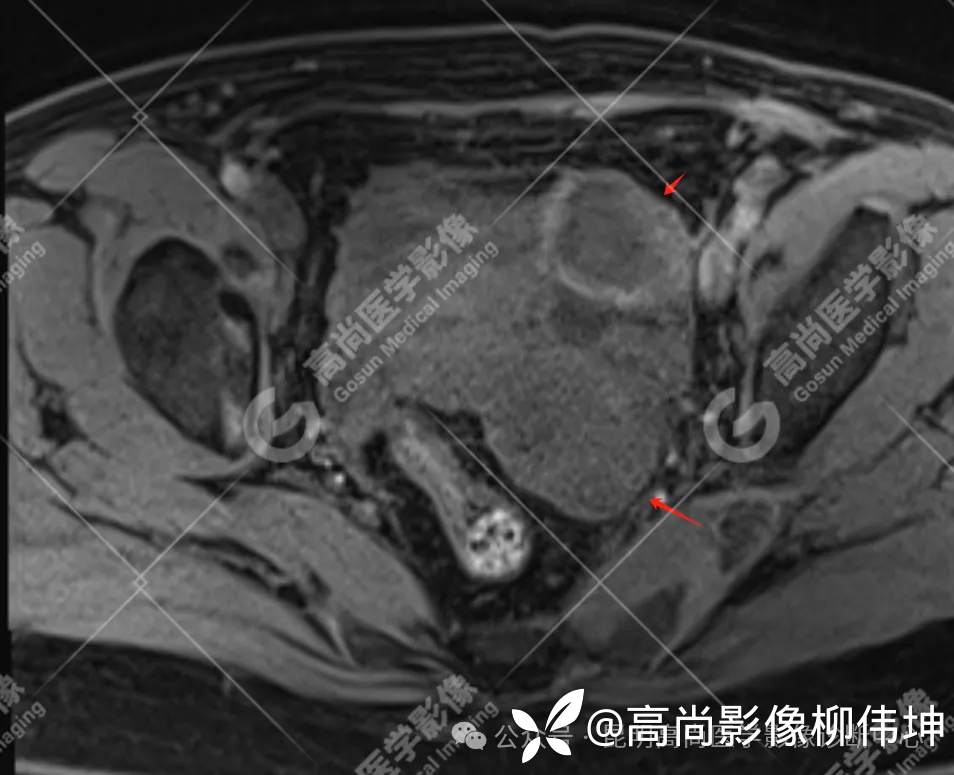

T2WI-fs-tra

(2)MRI表现:通常双侧发生,体积巨大,呈外生性、囊实性、乳头状生长,其内见大量长T1长T2液性信号影及线性分隔,囊壁厚薄不均,可见壁结节及不同比例实性成分,呈T1等信号,T2略高信号。扩散受限,DWI呈高信号,ADC呈低信号。增强扫描实性成明显强化。另外,常可检出腹水、腹膜增厚、盆壁及盆腔脏器受累、淋巴结肿大等表现。